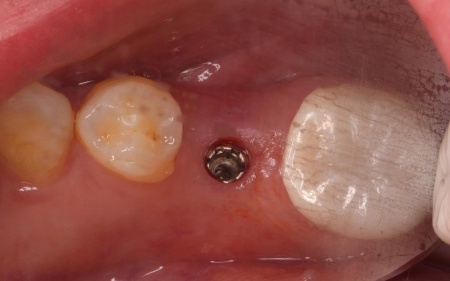

まず、左上下奥歯を慎重に抜きます。

続いてインプラント手術を実施し、インプラントを正しい位置と角度で顎の骨に埋め込みました。

インプラント手術後は経過観察を行い、インプラントが顎の骨に結合したことを確認したら、インプラント上部に取り付ける人工歯を作製するために精密な型取りを実施します。